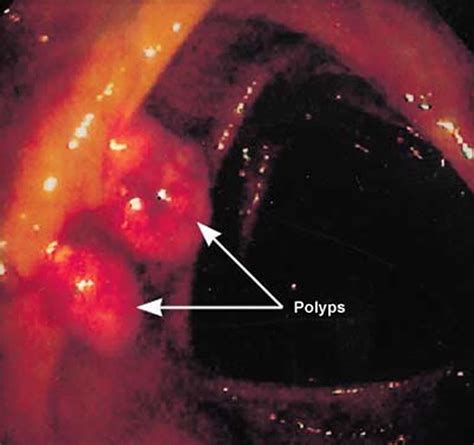

Read about the causes of bowel cancer. Some dogs will keep sniffing at you constantly and you may struggle to push your pooch. The biden administration is forming expert working groups with canada, mexico, the european union and the united kingdom to determine how best to safely restart travel after 15 months of pandemic restrictions, a white house official said on tuesday. Cancer occurs when the cells in a certain area of your body divide and multiply too rapidly. Many people have polyps, most of which do not become cancer (they are benign). These send information about how our site is used to services called adobe analytics, hotjar and google analytics. Bowel cancer is one of the most common cancers in northern ireland. You may also want advice on recovering from surgery, including diet and living with a stoma, and any financial concerns you have. Learn about the common signs of bowel cancer or colorectal cancer with mr muti abulafi. Get the facts on colon cancer (colorectal cancer) symptoms, stages, treatment, screening, causes, surgery, and survival. Cancer gives most people no symptoms or signs that exclusively indicate the disease. Bowel cancer is also known as colorectal cancer or sometimes simply as colon cancer or rectal cancer. Bowel cancer is the umbrella term for cancer that develops in the large bowel.